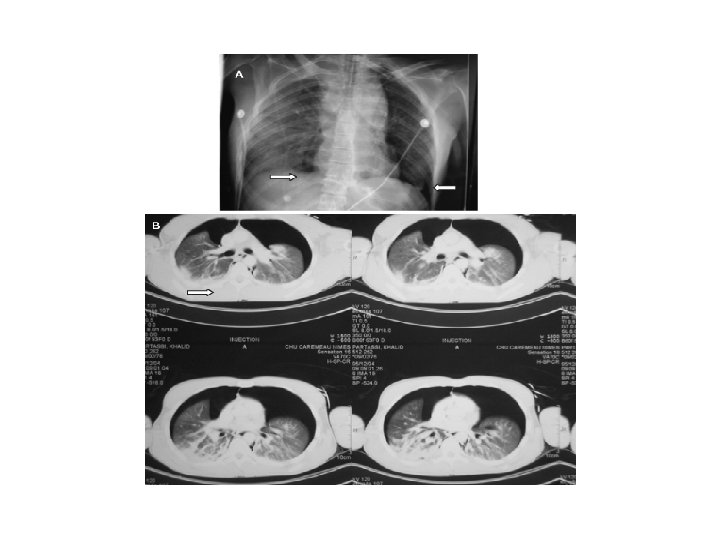

COMPLICATIONS DE LA VENTILATION ARTIFICIELLE – La présence d’un tube dans la trachée (corps étranger) et les aspirations trachéales sont source d’infections. – L’absence de toux, la position du patient et les inégalités de ventilation perfusion sont source d’atélectasies. – Les barotraumatismes et les voulotraumatismes pneumothorax, pneumo médiastin, emphysème sous cutané… -- Occlusion de la sonde ou de la canule par un bouchon muqueux ou autre asphyxie

A Atélectasie en bande Atélectasie des bases Atélectasie totale

PNEUMOTHORAX